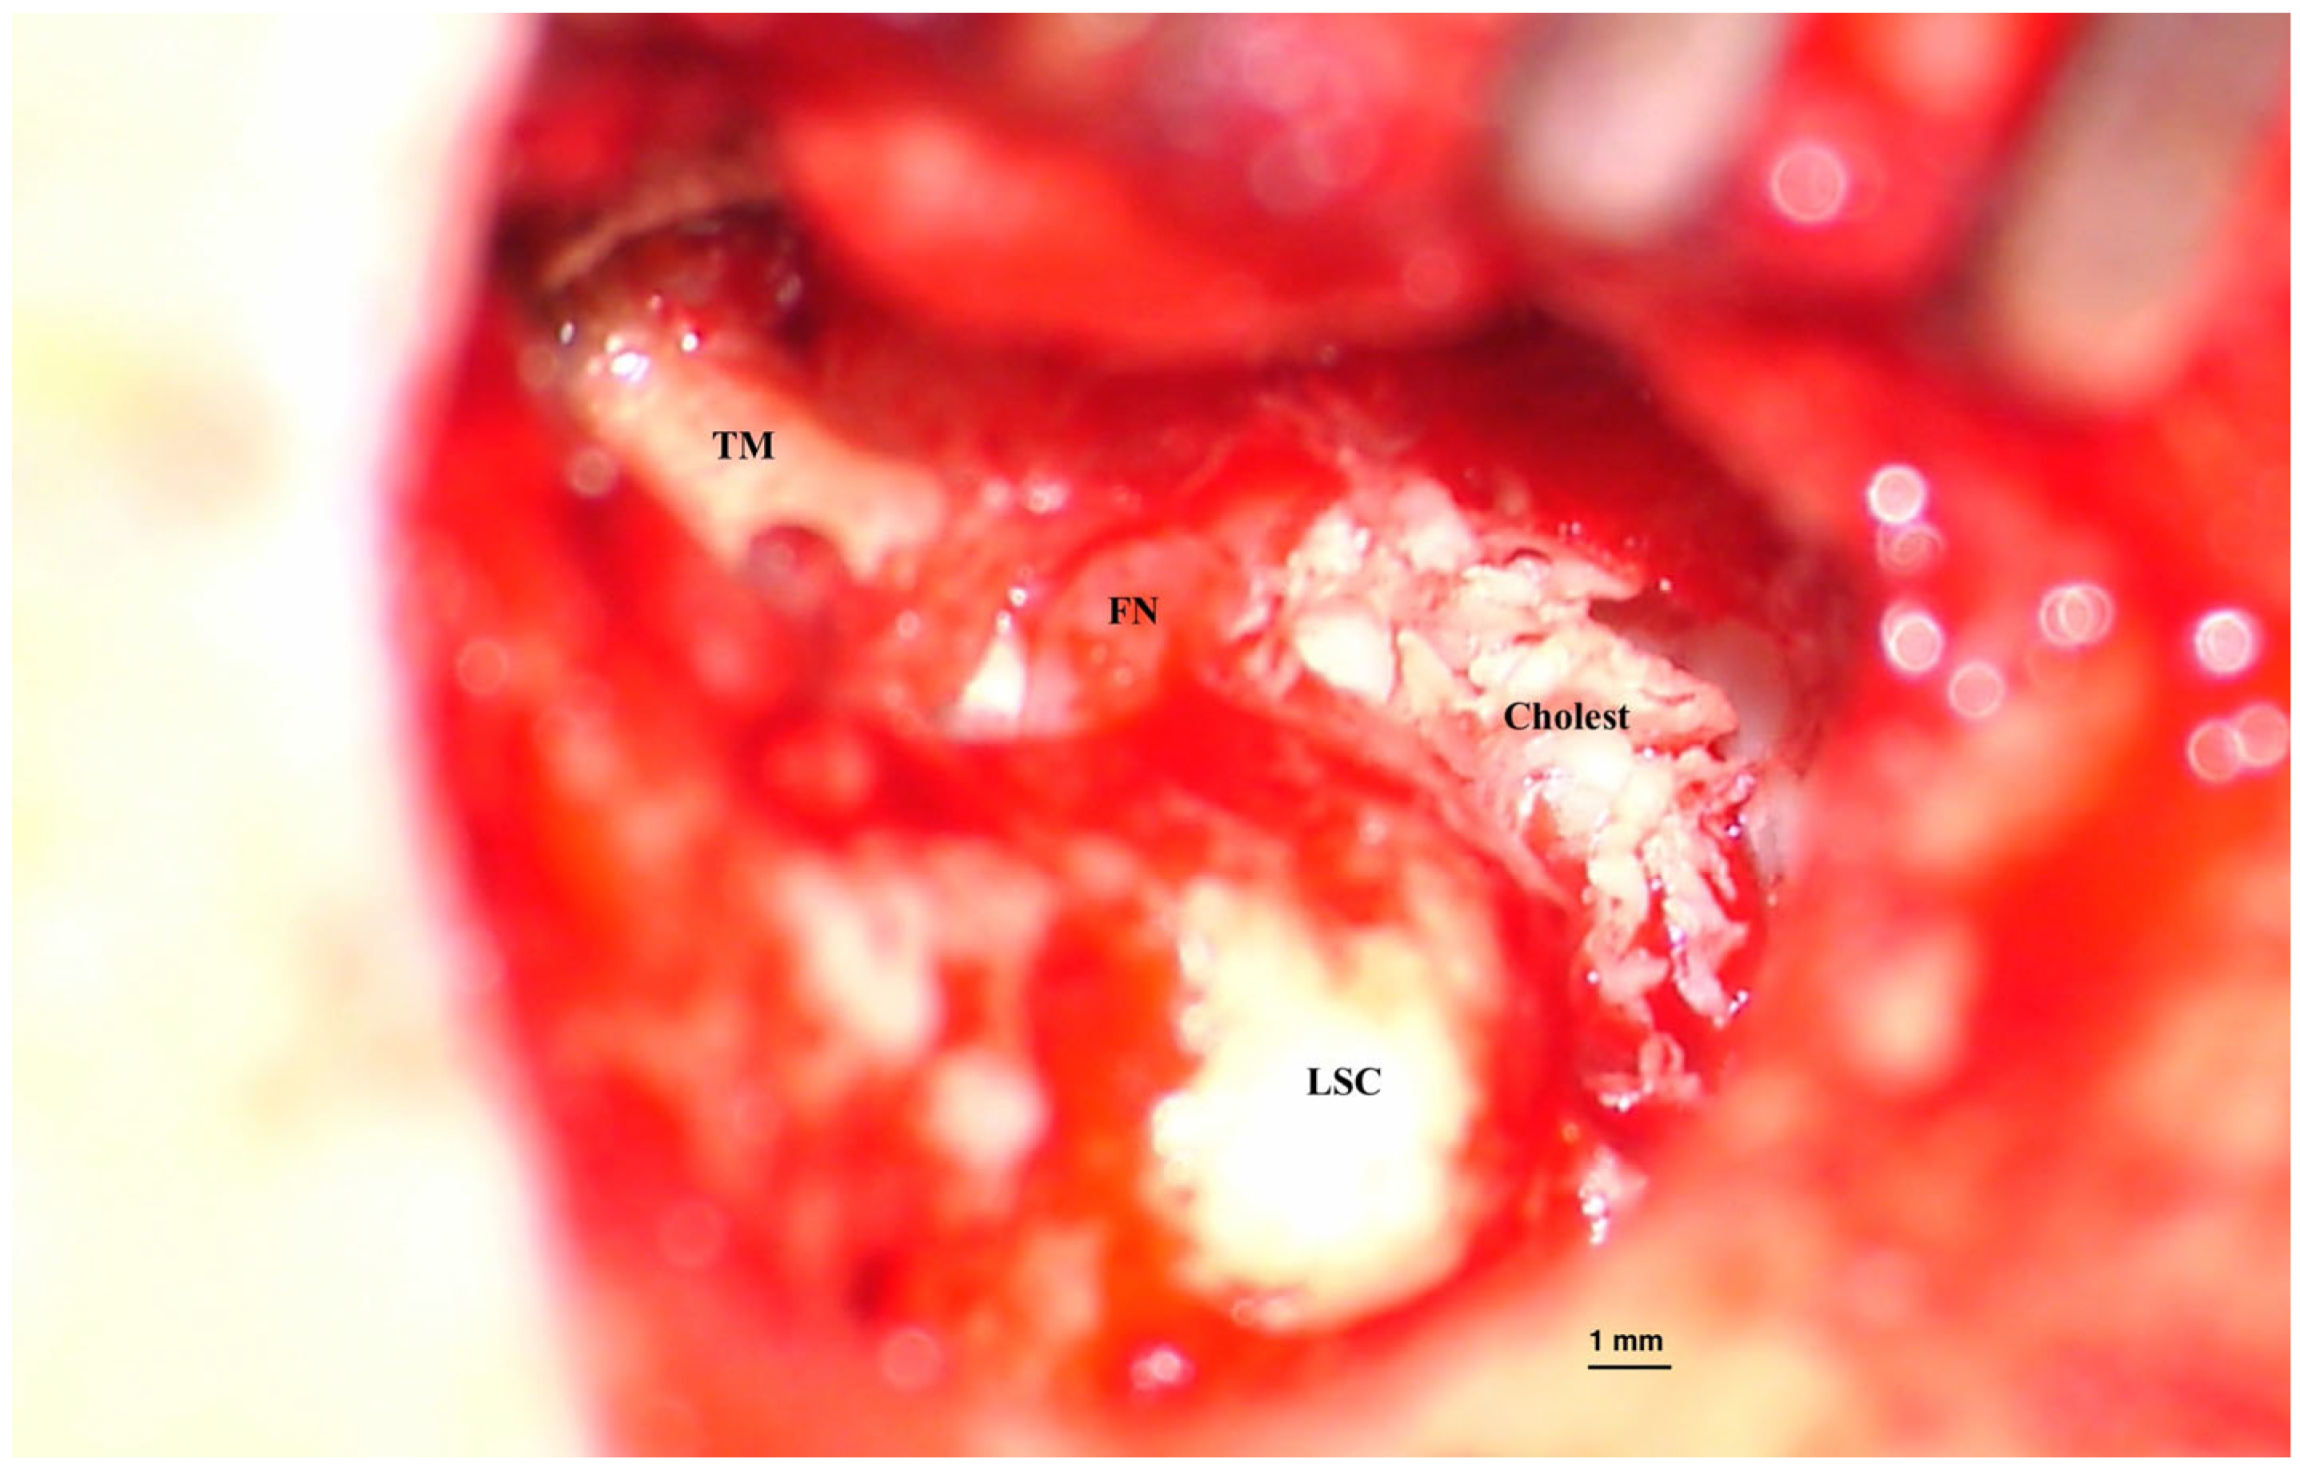

• Primary acquired, developed from a retraction pocket, due to Eustachian tube dysfunction or chronic otitis media (Figure 2);

Figure 2. Acquired cholesteatoma. Intraoperative image of surgery for an acquired cholesteatoma on the left ear. Epithelial matrix covered with keratin debris is visible on the inner wall of the middle ear and mastoid cavities. Bone erosions can be observed at the periphery of the lesion, suggesting the mechanism of invasion inside tympanomastoid spaces. (TM—Tympanic membrane, FN—facial nerve, LSC—Lateral semicircular canal). Picture taken with Zeiss TIVATO 700 microscope (ZEISS Microscopy, Jena, Germany). (from D.C.G’s. personal collection).